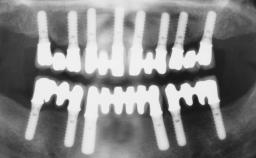

A 63-year-old female patient was referred to the University Medical Center in Groningen, Netherlands, for dental implant treatment. The patient had been edentulous in the upper jaw for 20 years. The remaining teeth in the lower jar had been removed two years before the consultation. The patient was wearing her first maxillary denture and her second mandibular denture; the latter was 1 year old at the time. The conventional upper denture had functioned satisfactorily for many years, but the patient complained about reduced stability and insufficient retention of her lower conventional denture. Her medical history revealed no significant findings. The intraoral examination revealed minor resorption of the maxillary alveolar process and extreme resorption of the mandibular alveolar process.

# of Implants | 2 |